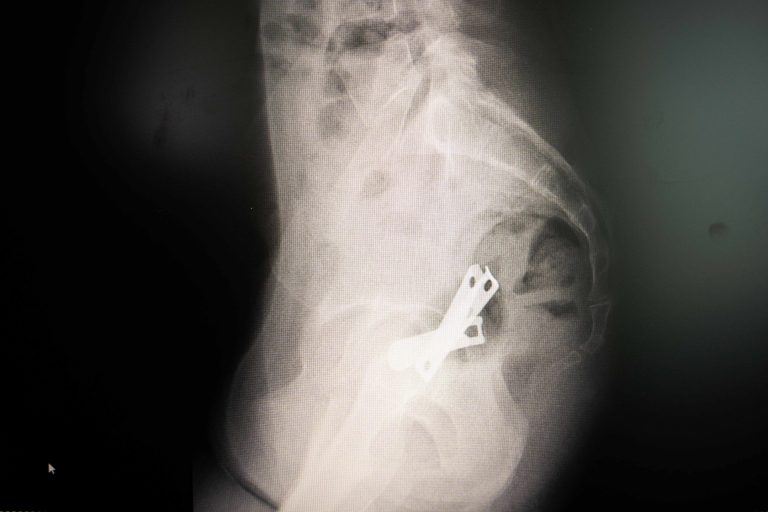

POS MB 708 3X-ray image showing a nail clipper inserted inside a uterus.POS MB 708 3$500

POS MB 708 19X-ray showing a nail clipper inside a uterus.POS MB 708 19$500